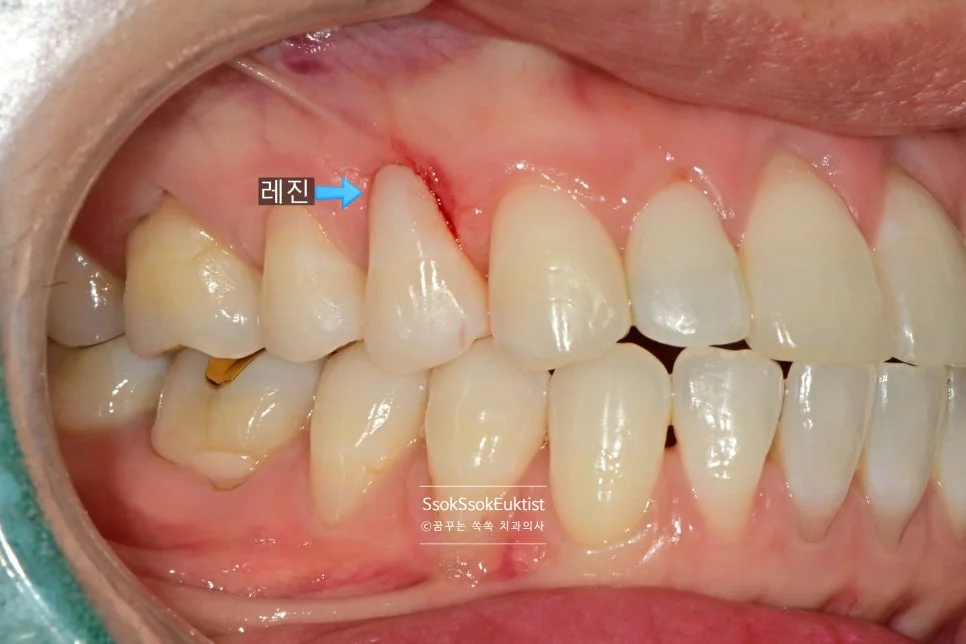

레진을 이용한 치경부 마모증 치료

레진 치료 전 — V자 형태의 치경부 마모증

치아의 목 부분이 패여져 있는 모습입니다. 형태를 보면 U자라기보다는 V자에 가깝고, 즉 강한 교합력에 의해 치아 목 부분이 패였네요.

치료 직후에 촬영한 사진인데요^^ 자연스러운 색상 그리고 모양인가, 잇몸을 과도하게 손상시키지 않았는가를 포인트로 보시면 됩니다!